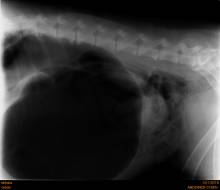

arrêt transit baryté chien dieppe

Les corps étrangers digestifs

L'ingestion de corps étranger est fréquente chez les carnivores domestiques. Les symptômes peuvent être très variés : vomissements aigues ou chroniques, diarrhée, absence de selles, douleurs abdominales plus ou moins marquées, traces de sang dans les selles, dysorexie ou anorexie totale, amaigri...